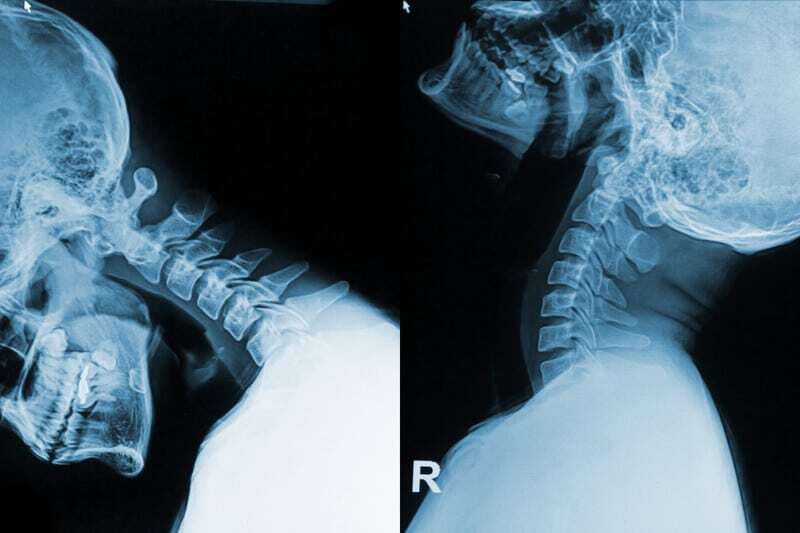

My MRI cannot confirm that I have whiplash associated disorders

If this has happened to you, you are not unique. While MRIs can show damage to the cervical spine and neck, it cannot tell whether or not your problems are being caused by what the MRI image shows. This was pointed out by a January 2022 paper (11) assessing the value of MRI in helping to diagnose whiplash associated disorders. The authors of this study wrote: “Many of these (WAD) patients receive treatment in primary care settings based upon clinical and diagnostic imaging findings. Despite the identification of different types of injuries in the whiplash patients, clinically significant relationships between injuries and chronic symptoms remains to be fully established.” The are some of the problems the radiologists looked for:

- Kyphosis. The cervical spine is either straight “military neck” or has begun to curve in the opposite, non-natural direction.

- Lateral atlas displacement

- Alar ligament signal changes (damage),

- Transverse ligament signal changes (damage),

- Lateral joint degeneration C0/C1,

- Lateral joint degeneration C1/C2,

- Reduced disc height

- Modic changes (bone marrow lesions),

- Uncovertebral joint degeneration, (the C3 to C7 group).

- Facet joint degeneration,

- Neural foraminal stenosis,

- Spinal canal stenosis and,

- Vertebral artery loop. Changes in the neck have caused the vertebral artery supplying blood to the brain to have a loop or stretch in it.

Despite seeing these damages, the radiologists could not determine if any of these injuries prevented the natural flow of cerebrospinal fluid (the fluid of the brain that provides protection and nutrients for the brain). A characteristic of whiplash associated disorder.

Cervical neck ligament weakness causing loss of curvature of the cervical spine

In their April 2019 update, Cervical (Whiplash) Sprain in the publication StatPearls (10) from the National Center for Biotechnology Information, U.S. National Library of Medicine, Kara J. Bragg of the Mayo Clinic and Matthew Varacallo, Department of Orthopaedic Surgery, University of Kentucky School of Medicine wrote:

“(Whiplash) injury occurs in three stages with a rapid loss of lordosis. (Lordosis means an abnormal neck curvature. It can mean too much of a curve or that the curve is bent or pointed the wrong way, this is called reverse cervical lordosis.)

Both the upper and lower spines experience flexion (hypermobility) in stage one. In stage two the spine assumes an S-shape while it begins to extend and eventually straighten to make the neck lordotic again. The final phase shows the entire spine in extension (hyper-extended) with an intense sheering force that causes compression of the facet joint capsules.Studies with cadavers have shown the whiplash injury is the formation of the S-shaped curvature of the cervical spine which induced hyperextension on the lower end of the spine and flexion of the upper levels, which exceeds the physiologic limits of spinal mobility.”